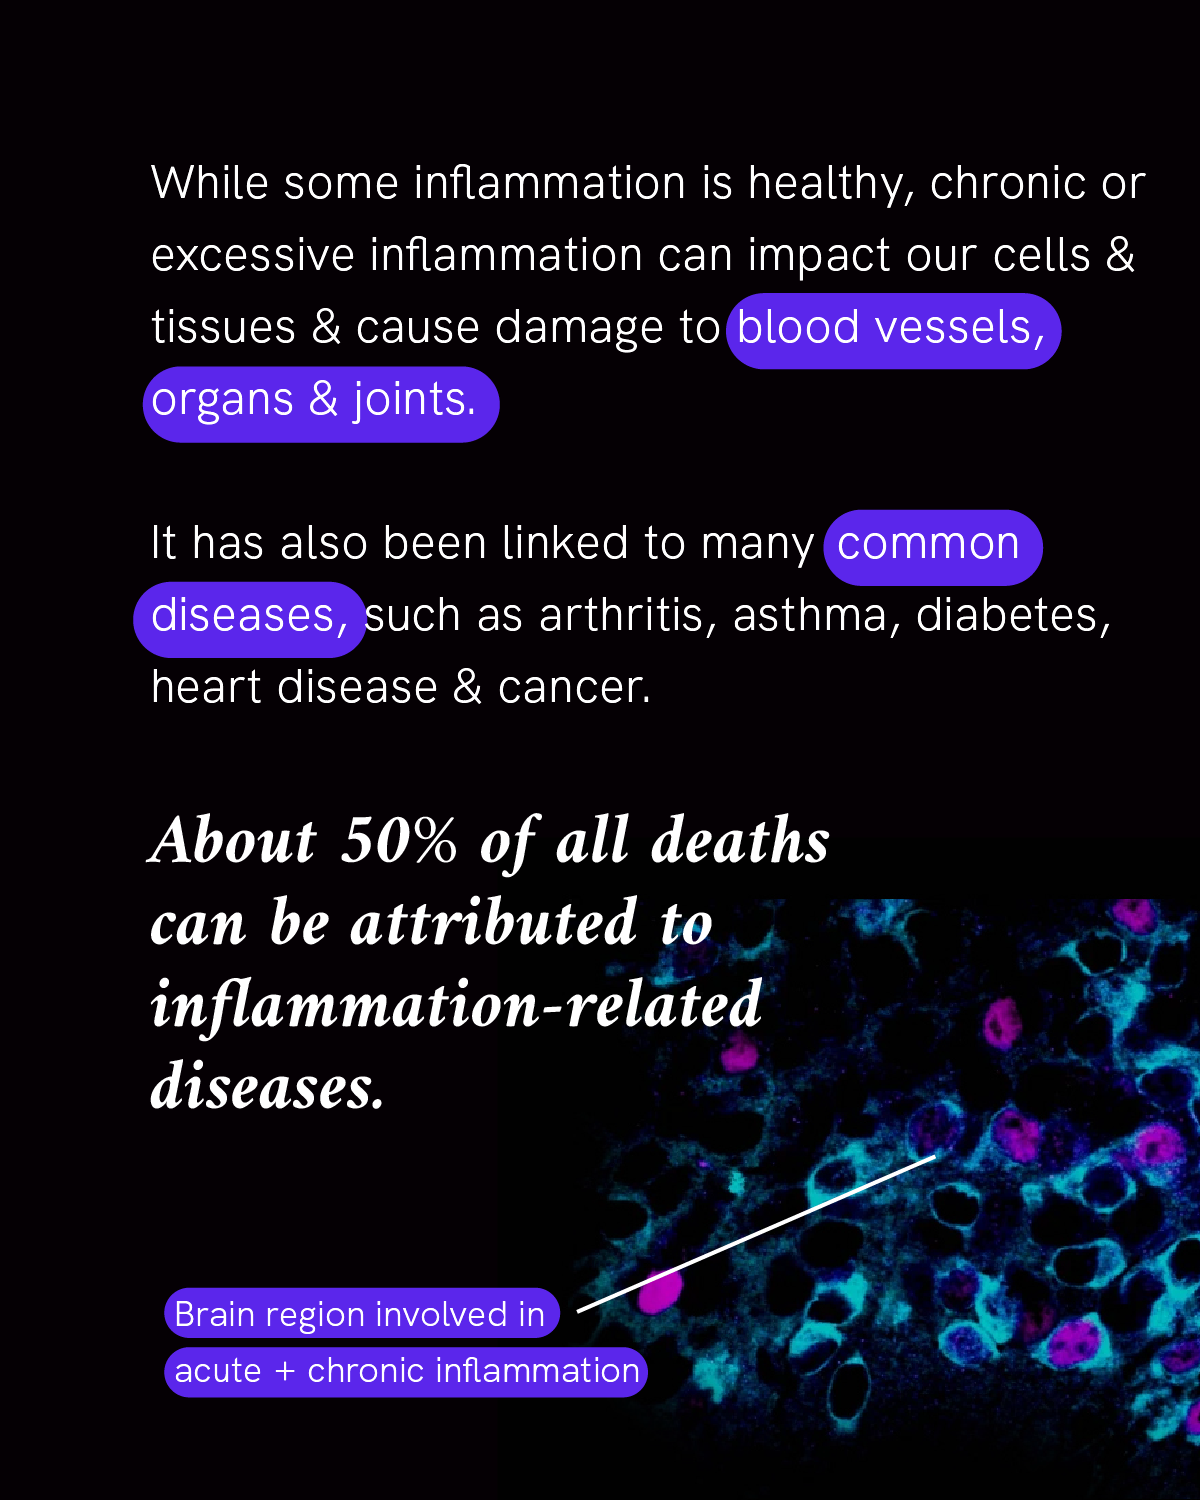

Inflammation is our body’s first line of defense against injury or infection by harmful viruses, bacteria or other pathogens. It’s an important response from the immune system to try to minimize injury or infection and begin the healing process, but too much inflammation at the wrong place or time can become a problem.

About 50% of all deaths can be attributed to inflammation-related diseases — including cancer, heart disease and dementia. If scientists can watch the human immune system in action to see how our cells and tissues are impacted, they can figure out ways to control inflammation.

Researchers at the Chan Zuckerberg Biohub Chicago are engineering new tools to measure inflammation in living tissues. This will enable them to study the fundamental causes of inflammation — how it starts, why it keeps going, and how to turn it around so that we can prevent disease before it starts, or find ways to treat it at an earlier stage.